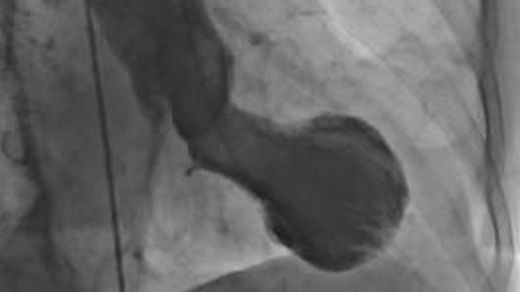

El síndrome del corazón roto también es conocido como el “síndrome de takotsubo“, por la similitud de la forma del corazón de las personas con esta condición con la olla japonesa del mismo nombre.